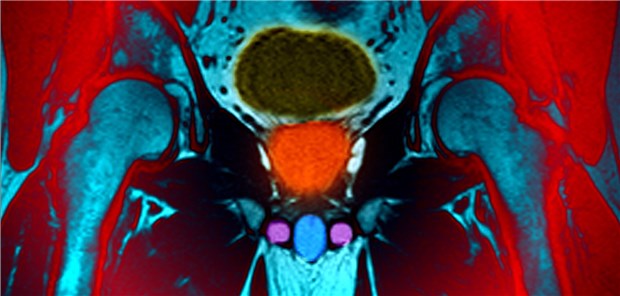

Magnetresonanz-Aufnahme des männlichen Beckens: Die Prostata ist orange eingefärbt.

© Living Art Enterprises

Prostatakrebs

Mit MRT lassen sich Biopsien vermeiden